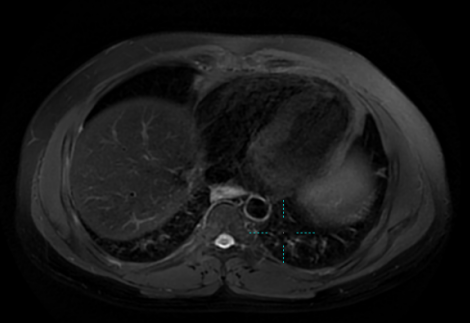

2022.03.11PET-CT:肝VIII段低密度影,大小约3.7cm×2.8cm

2022.05.08化疗两周期后复查肝脏MRI:肝VIII段低密度影,大小约2.3cm×1.9cm